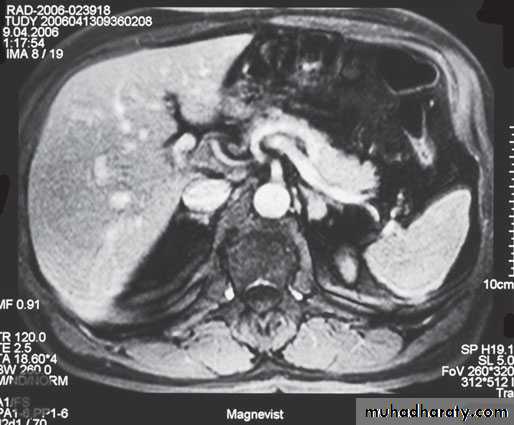

2- imaging study for the localization of the phaeochromocytoma and/or metastases. MRI is preferred because contrast media used for CT scans can provoke paroxysms.

3-MRI and CT are equally effective in distinguishing adrenocortical adenoma from carcinoma .